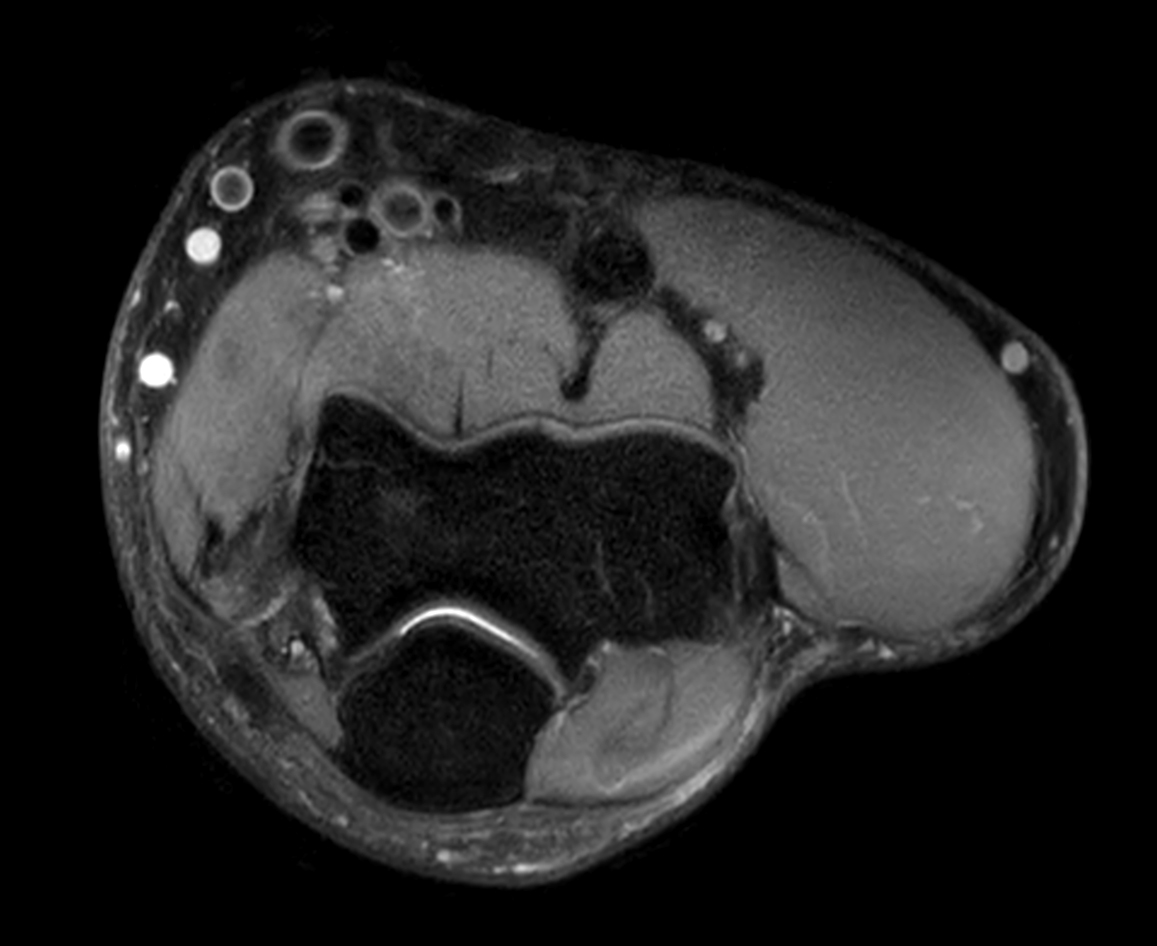

Axial PDw mDIXON XD TSE (In Phase)